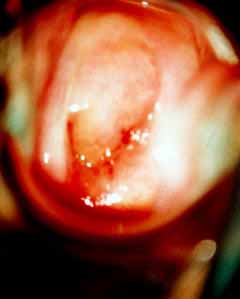

Κολποσκοπικές εικονες για τις αναγκες του forum.